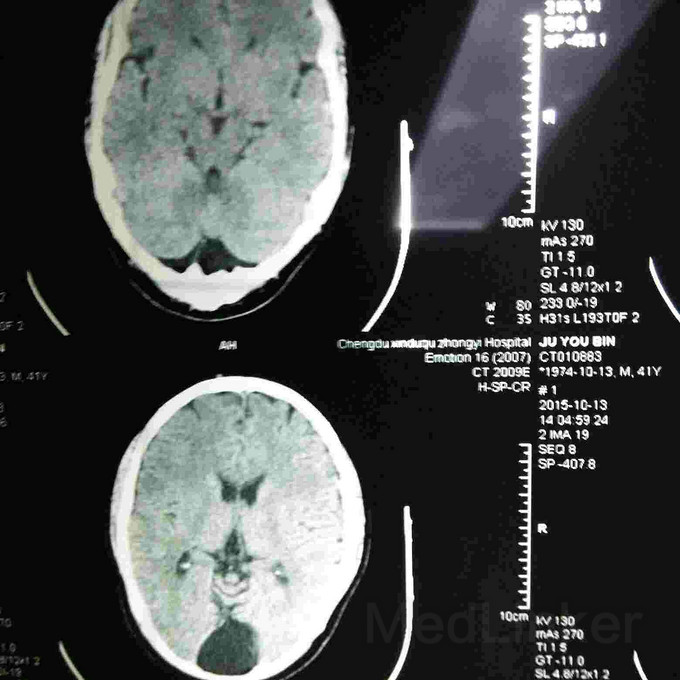

病患42、男性,近半年偶感轻度头胀,记忆力下降,作CT检查如下几图,报告单说是蛛网膜下腔囊肿,请问是这个病吗?目前需要注意什么问题?治疗有什么方法?